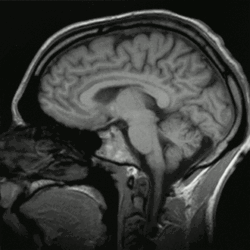

More recent research has sought to study the mindful brain (Hölzel et al., 2011; Taylor et al., 2011). Taylor et al. (2011) investigated the neural responses of individuals who practice mindfulness to emotional stimuli and compared results between experienced and beginner practitioners. Their results indicated that extensive mindfulness practice fosters emotional stability and modulates a number of regions in the brain that are involved in the neural responses to emotional experiences.

To confirm what mindfulness theory has long purported, the results of the study by Taylor et al. (2011) indicate that long term mindfulness practice induces brain activity patterns that are associated with acceptance of emotional stimuli and lower levels of interference from internal states (Taylor et al., 2011). The authors argue that this possibly points to better awareness of the here-and-now. Conversely, their results also indicate that less experienced mindfulness practitioners show brain activity that relates to voluntary regulation of emotion, which infers less acceptance of emotional states, and lower levels of emotional stability (Taylor et al., 2011).